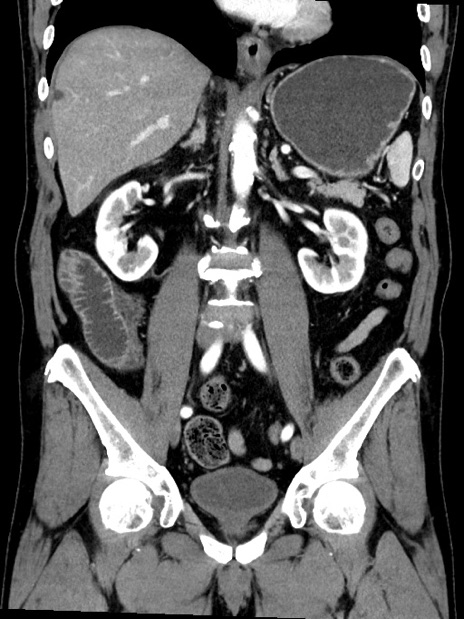

症例35(冠状断像)

【症例】70歳代 男性

【主訴】腹部膨満、嘔吐

【現病歴】昨日より腹部膨満感出現。本日増悪し、仙痛出現。嘔吐あり、受診。

【既往歴】糖尿病、胆摘後

【身体所見】BP 149/80mmHg、HR 74/min、BT 35.9℃、腹部:膨満、軟、圧痛なし。腸雑音減弱あり。上腹部正中切開瘢痕あり。

【データ】WBC 13500、CRP 1.72